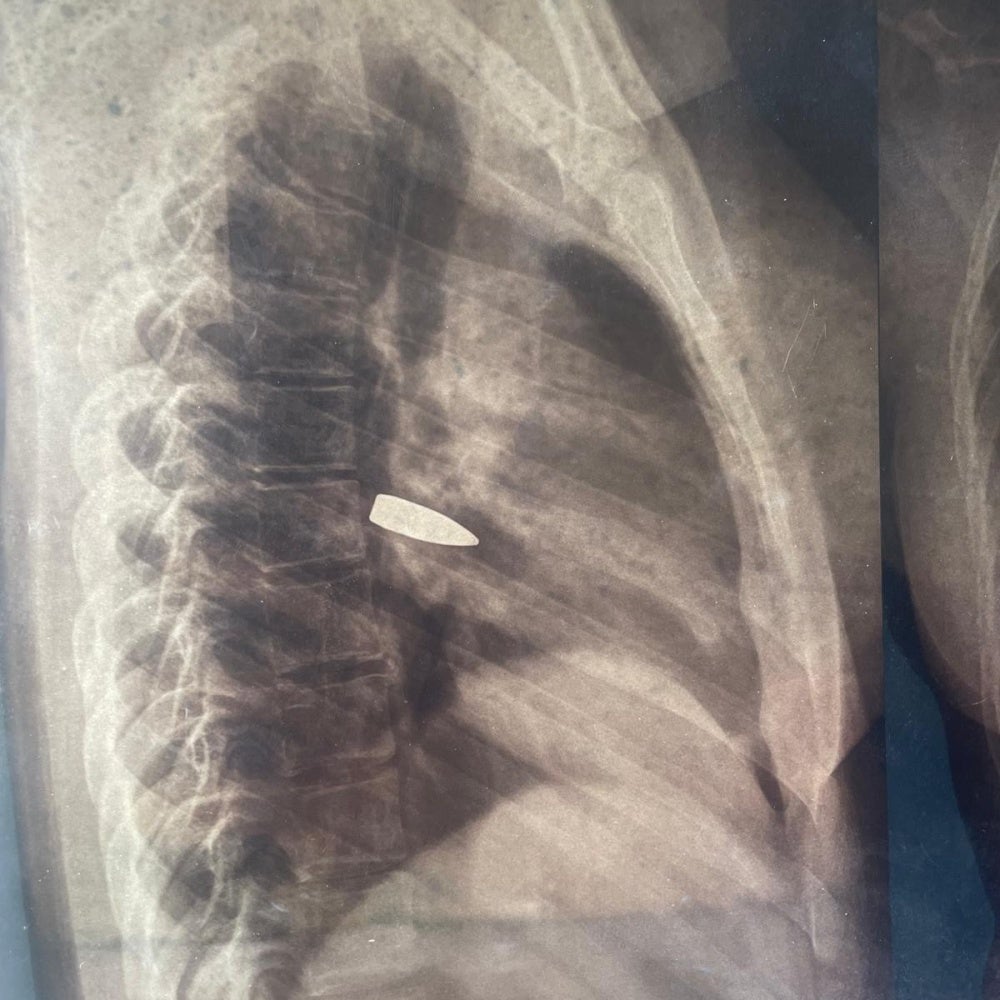

The organizations saw x-rays from six people who had bullets lodged in their bodies. Three of the people had not yet had the bullets removed at the time of interview in August.

Remnants of a projectile that fell on a house in the Ridina district of N'Djamena on May 9, 2024, following the announcement of the provisional results of the Chad presidential elections. © 2024 Private

Remnants of a projectile that fell on a house in Moundou, southern Chad, on May 9, 2024, following the announcement of the provisional results of the Chad presidential elections. © 2024 Private